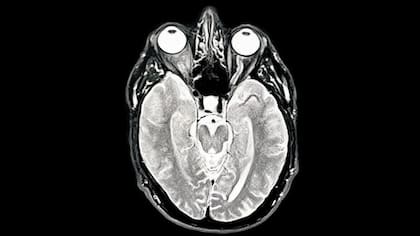

El cerebro pasa por cinco fases distintas en la vida, con puntos de inflexión clave a los 9, 32, 66 y 83 años, afirma un grupo de científicos. Los hallazgos forman parte de un estudio en el que participaron alrededor de 4000 personas de hasta 90 años, quienes se sometieron a escáneres que mostraron las conexiones entre sus neuronas.

Investigadores de la Universidad de Cambridge demostraron que el cerebro permanece en la fase adolescente hasta los 30 años, cuando alcanzamos nuestro máximo potencial. Afirman que los resultados podrían ayudarnos a comprender por qué el riesgo de sufrir trastornos de salud mental y demencia varía a lo largo de la vida.

Estos patrones solo se revelaron ahora gracias a la cantidad de escáneres cerebrales disponibles en el estudio, publicado en la revista Nature Communications.